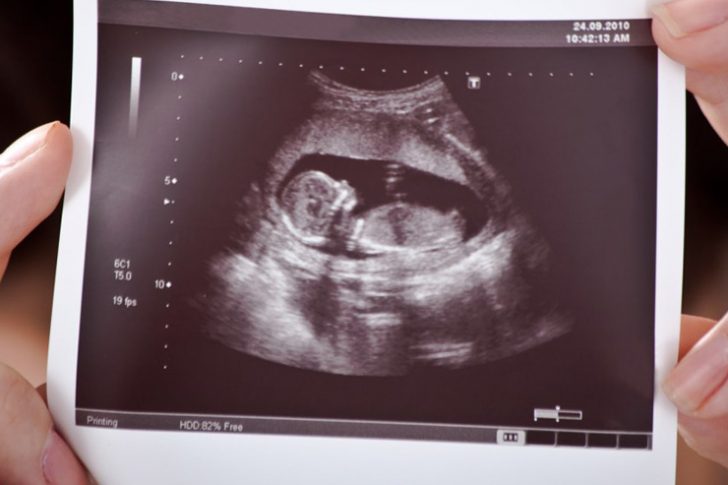

Down sendromu Tarama Testleri ENSE KALINLIĞI TESTİEnse kalınlığı testi nedir? Gebeliğin 11-14 haftaları arasında ultrasonografi ile yapılan basit bir testtir. Uygun pozisyonda bebeğin ense kalınlığı…

Renkli Doppler-Dört Boyut ve diğer-Ailelere bilgi Ülkemizde kısmen de yanlış olarak, gebeliğin 11-14 veya 15-21 haftaları arasında özellikle Down Sendromu, diğer kromozom anormalliklerini ve doğumsal…

GEBELİKTE ULTRASONOGRAFİ MUAYENESİ – Ailelere bilgi Gebelik sırasında, fetus (doğmamış bebek) ile ilgili olası problemlerin tanınması ve bunlara göre önlem alınabilmesi için ultrasonografi ile bazı…